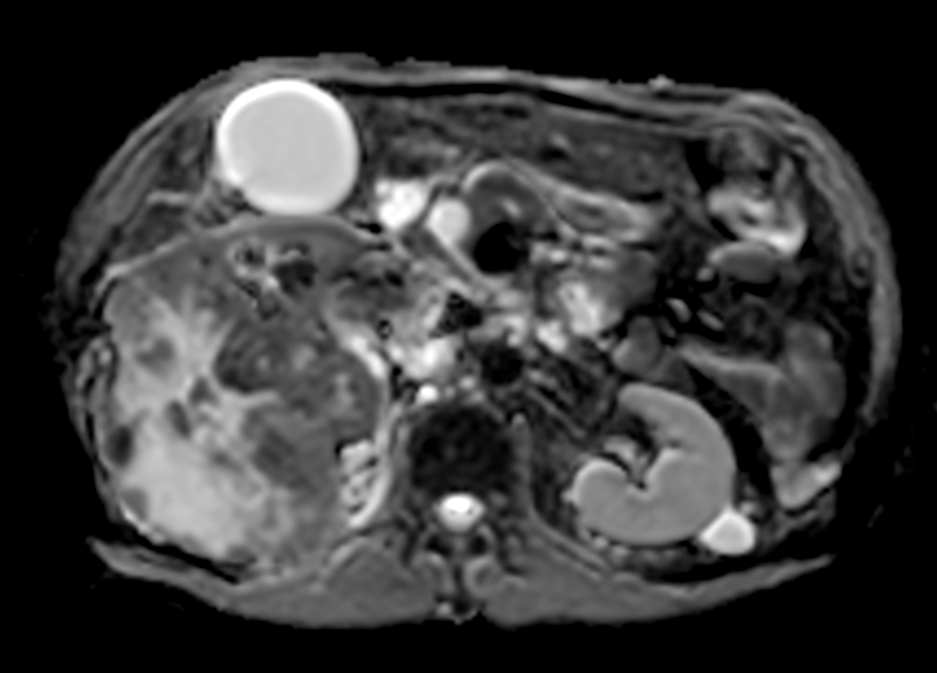

Patient with kidney tumor. ExamCard includes Compressed SENSE to shorten the breath hold time, VitalEye for touchless respiratory sensing, mDIXON XD FFE to acquire up to four image types in one single scan, DWIBS to achieve high contrast between background and lesions and bTRANCE for non-contrast time-resolved imaging.

T1w FFE mDIXON XD (In Phase) Compressed SENSE